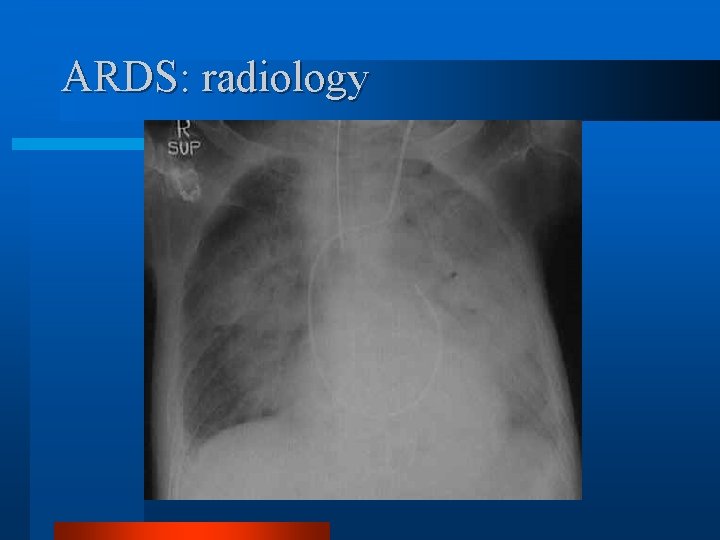

ARDS: radiology